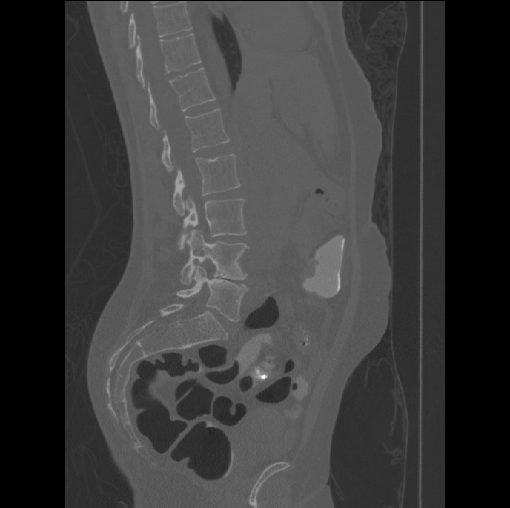

Spinal imaging via computed tomography (CT), magnetic resonance imaging (MRI), radiography, ultrasound, positron emission tomography (PET), and other radiologic imaging modalities is essential for noninvasively visualizing and assessing spinal pathology. Computational methods support and enhance a physician’s ability to utilize these imaging techniques for diagnosis, noninvasive treatment, and intervention in clinical practice. Analysis algorithms developed in the field of computer vision, computer graphics, signal processing, and machine learning have been adapted to analyze spinal images (Li et al., 2015). Conventionally, CT is preferred to study the spine due to a high bone-soft tissue contrast. There are diverse image appearance variations due to differences in vertebral position, metal artifacts and spinal diseases, etc., challenging the analysis algorithms. Fig. 1 gives some examples of these various conditions.

Images

GT

Predictions

We calculate the two metrics of each vertebra, and the results are reported in Table 2. On the one hand, our experimental results are close to those reported in reference (Sekuboyina et al., 2020) with the same model (nnUnet), verifying the high quality of our annotations. On the other hand, Table 2 shows it is difficult to segment the diseased vertebrae (the DSC of L6 is almost 0). Specifically, the existence of L6 confuses the model, resulting in prediction dislocations (see the last row in Fig. 4). Thus, our labeled dataset, which contains many L6 cases, is very valuable for the diseased vertebrae segmentation (we have stated those cases that are hard for annotation in the readme.txt file). Table 2 illustrates that the model trained with our annotations can achieve good performance on our CTSpine1K dataset but a much worse performance on the VerSe Challenge datasets, which explains there is an obvious domain gap between our annotated dataset and the public dataset. We infer the reason is that the COlONOG dataset is based on an empty stomach and colon, confusing the deep learning model by the changes of air content in the abdomen (see Fig. 3). Therefore, our annotations are a good complement to the existing datasets.

3.2.2 Qualitative results.

Some visualization results are presented in Fig. 4, where we can observe that the baseline model can achieve excellent segmentation results. Nevertheless, some failed predictions occur when spinal diseases exist, especially sacral lumbarization and lumbar sacralization. Besides, the image’s resolution of Z direction is closely related to the results, and a lower resolution leads to worse results. Maintaining a reasonable performance for a low resolution is a research challenge. Image superresolution (Peng et al., 2020) might be worth exploring.